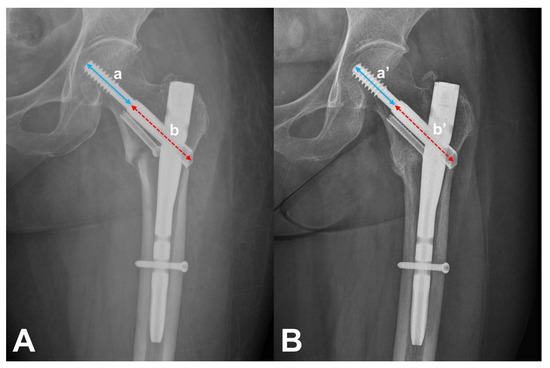

2.1. Measurement of N–C Difference